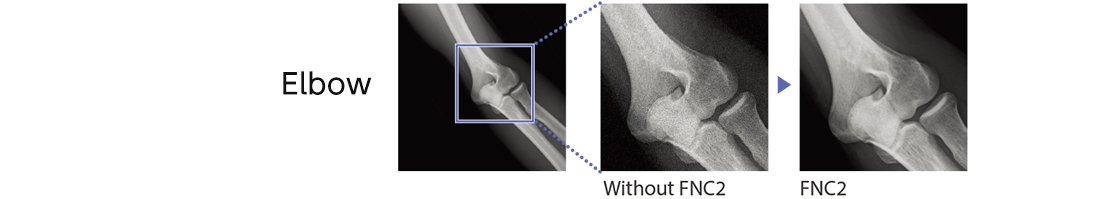

FNC2 - New Flexible Noise Control

suppressing complex noise components from the image

FNC2 extracts the noise component in the image by recognizing complex line and dot components as well as estimating the noise amount in relation to body thickness.